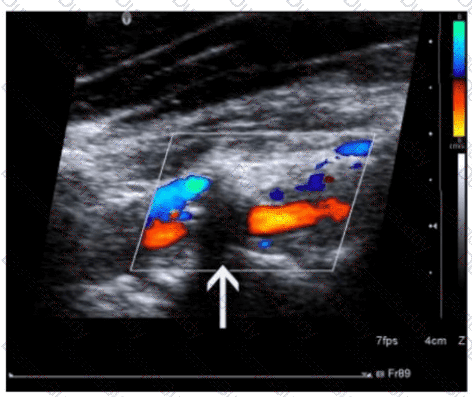

Questions 30

What adjustment is needed to optimize the color in the image below?

SPI Question 30

Options:

A.

Decrease gain

B.

Increase wall filter

C.

Decrease persistence

D.

Increase pulse repetition frequency

Buy Now